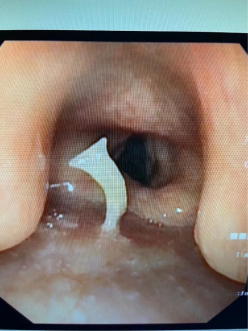

喉镜深度不够

改为气管镜下取出一根大鱼刺

一位婆婆在进食糯米豌豆饭时不慎呛入一颗豌豆进入气管,急诊行气管镜取出异物。

更有甚者,某ICU患者一排假牙掉至气管内导致管腔堵塞后感染,在支气管镜下用异物钳将假牙夹了出来。